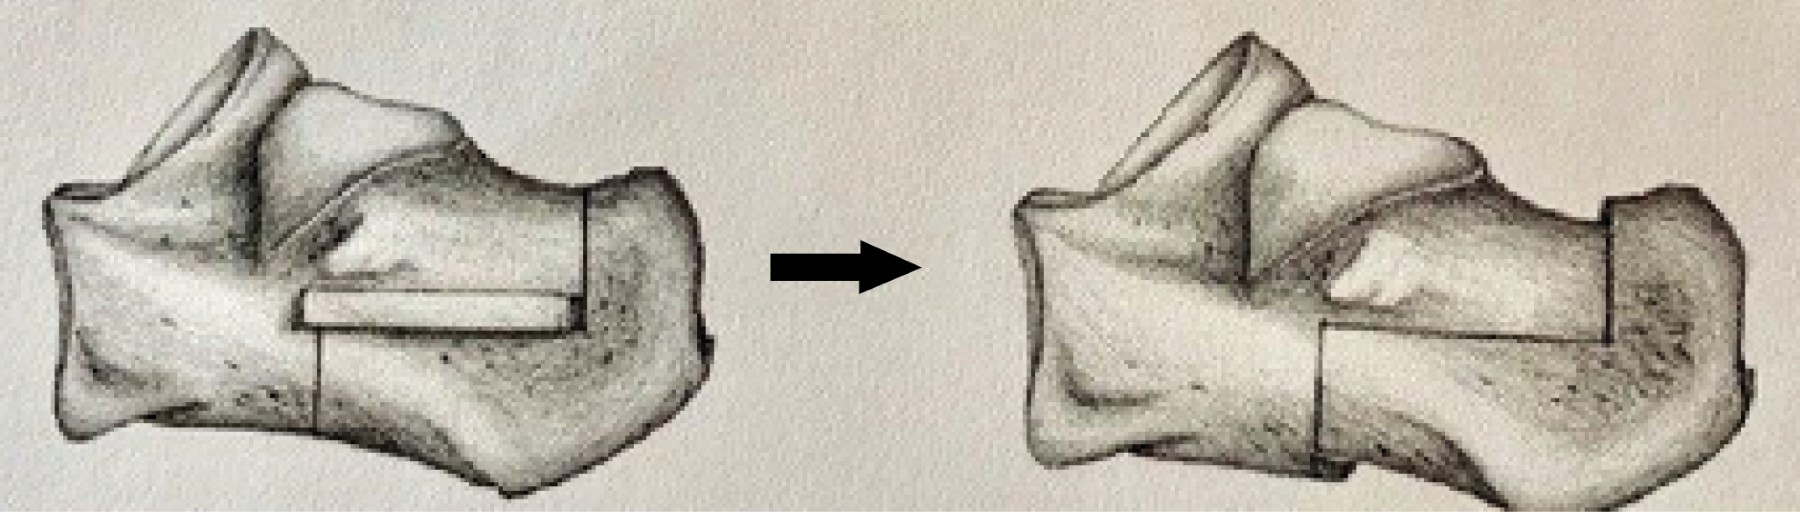

Figure 1